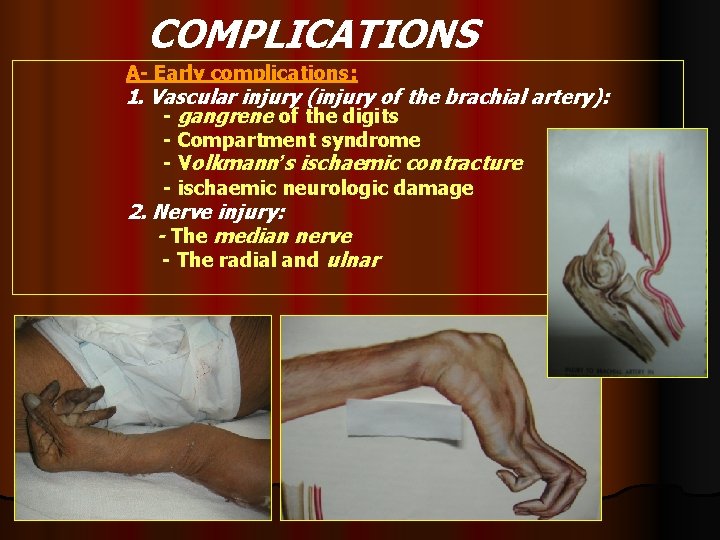

COMPLICATIONS A- Early complications: 1. Vascular injury (injury of the brachial artery): - gangrene of the digits - Compartment syndrome - Volkmann’s ischaemic contracture - ischaemic neurologic damage 2. Nerve injury: - The median nerve - The radial and ulnar